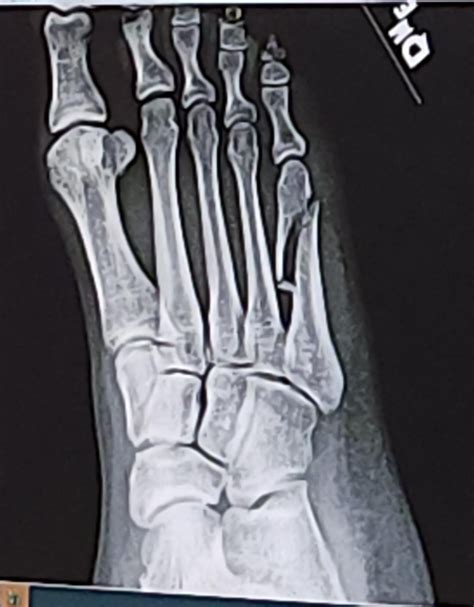

Diagnosing a Fifth Metatarsal Fracture

Diagnosing a Fifth Metatarsal Fracture typically involves a combination of physical examination and imaging tests. The diagnostic process may include:

• Physical Examination: A healthcare provider will examine the foot, checking for swelling, tenderness, and deformity.

• X-Rays: X-rays are the primary imaging tool used to confirm the presence and location of the fracture.

• CT Scans or MRIs: In some cases, more detailed imaging such as CT scans or MRIs may be required to assess the extent of the fracture and plan treatment.